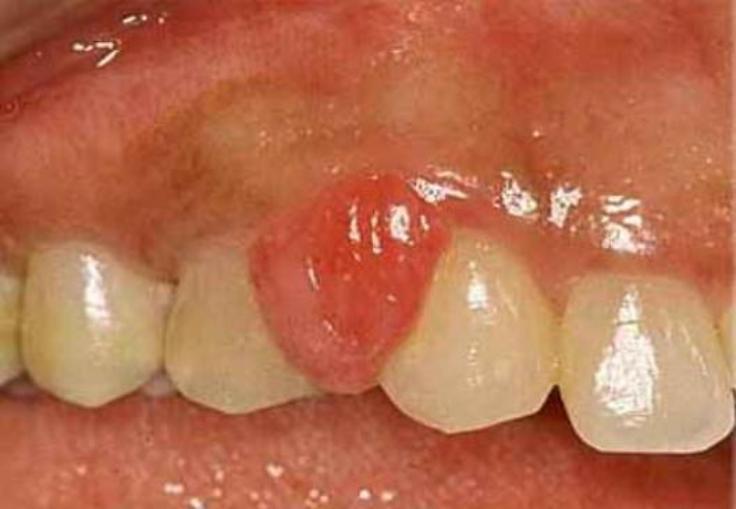

1. Luteoma del embarazo

1. Quistes de la teca luteínica